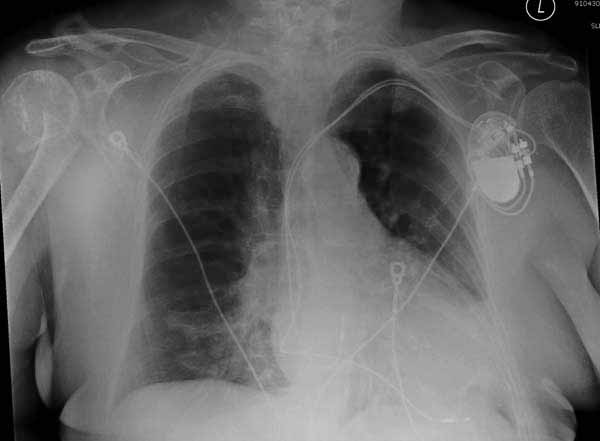

Здесь результат похожего случая, больная 87 лет, отягощенная сердечными делами и два года назад установка pacemaker и нескольких стентов. На третий день, сегодня утром сделали операцию. Послеоперационный псевдовывих связанный с релаксацией мышц и общим обезболиванием.